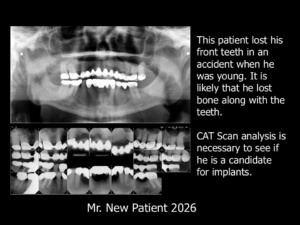

I suspected that Mr. New Patient may not be a good candidate for implants. It is likely that substantial anterior bone was lost in the accident along with his front teeth. It is difficult to ascertain whether Mr. New Patient is a good candidate for implants based on the full series of X-Rays and panorex pictured here. As a result, I requested that an oral surgeon conduct a CAT scan analysis and provide an assessment. If Mr. New Patient turns out not to be a good candidate for implants in the front of his mouth, it is reasonable to conclude that he would also have a poor prognosis for an All-on-Four case.